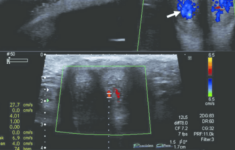

Siêu âm nam khoa: Những điều nam giới cần biết

Siêu âm vẫn được xem là một trong những phương tiện chẩn đoán hình ảnh lâu đời nhất. Tuy nhiên, đây cũng được xem là phương tiện hỗ trợ...